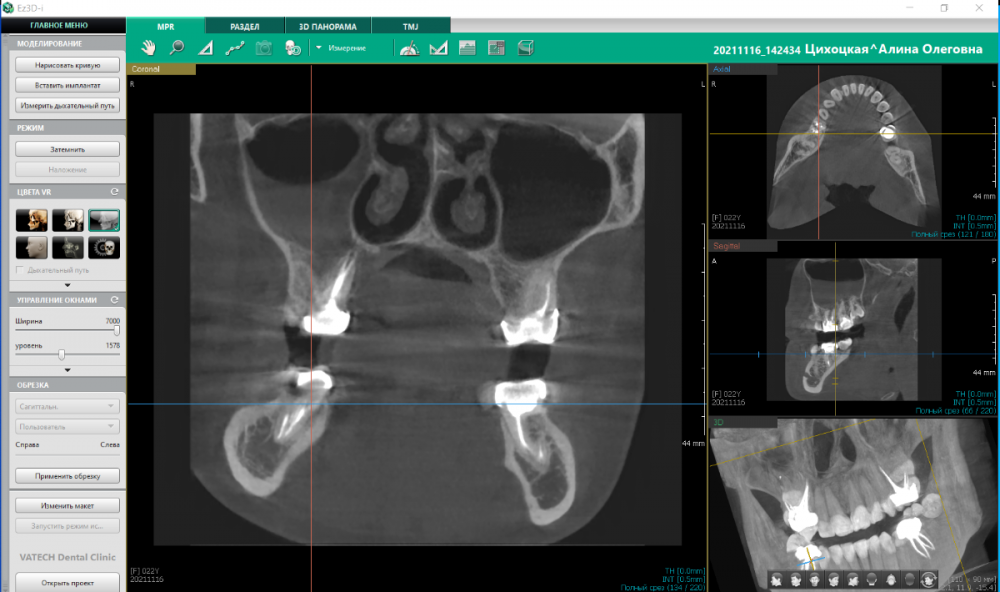

mralicemr Опубликовано 17 ноября, 2021 Автор Поделиться Опубликовано 17 ноября, 2021 (изменено) Дополняю. Посетила другого терапевта вчера, 16.11.2021. Она настояла на КТ, сказав, что снимок неинформативен. Сделали КТ. Выводы (с ее слов) следующие: 1. Шестёрка под коронкой. Воспаление подтверждено. Лечение - под микроскопом, без гарантии, вероятность удачного стечения обстоятельств по итогу - 30%. Отправила на консультацию к хирургу, к нему записались на следующую неделю (раньше окошек не было). И лору, по пункту 2 (ниже). 2. Дно между шестёркой и пазухой отсутствует. Пазуха наполовину заполнена чем-то. Чем - врач не сказала. 3. Сказала, боль точно не от семёрки и не от зуба мудрости. Боль либо от воспаления в шестёрке под коронкой, либо от воспаления в гайморовой пазухе. Итог: консультация хирурга, затем консультация лора. Вопросов много, но главный - насколько ситуация вообще критична? Предполагаю, зуб логичнее удалять, предварительно пройдя лечение у ЛОРа? На данный момент перешла с ибупрофена и кетанова на нимесил 1 раз в день. Зуб почти перестал беспокоить. Остался только насморк и головная боль, но после выявленных новостей на КТ состояние испуганное. За любую консультацию буду благодарна. Как сделать панорамный снимок из КТ - не разобралась, могу подгрузить ссылку на КТ, если необходимо. Изменено 17 ноября, 2021 пользователем mralicemr Ссылка на комментарий